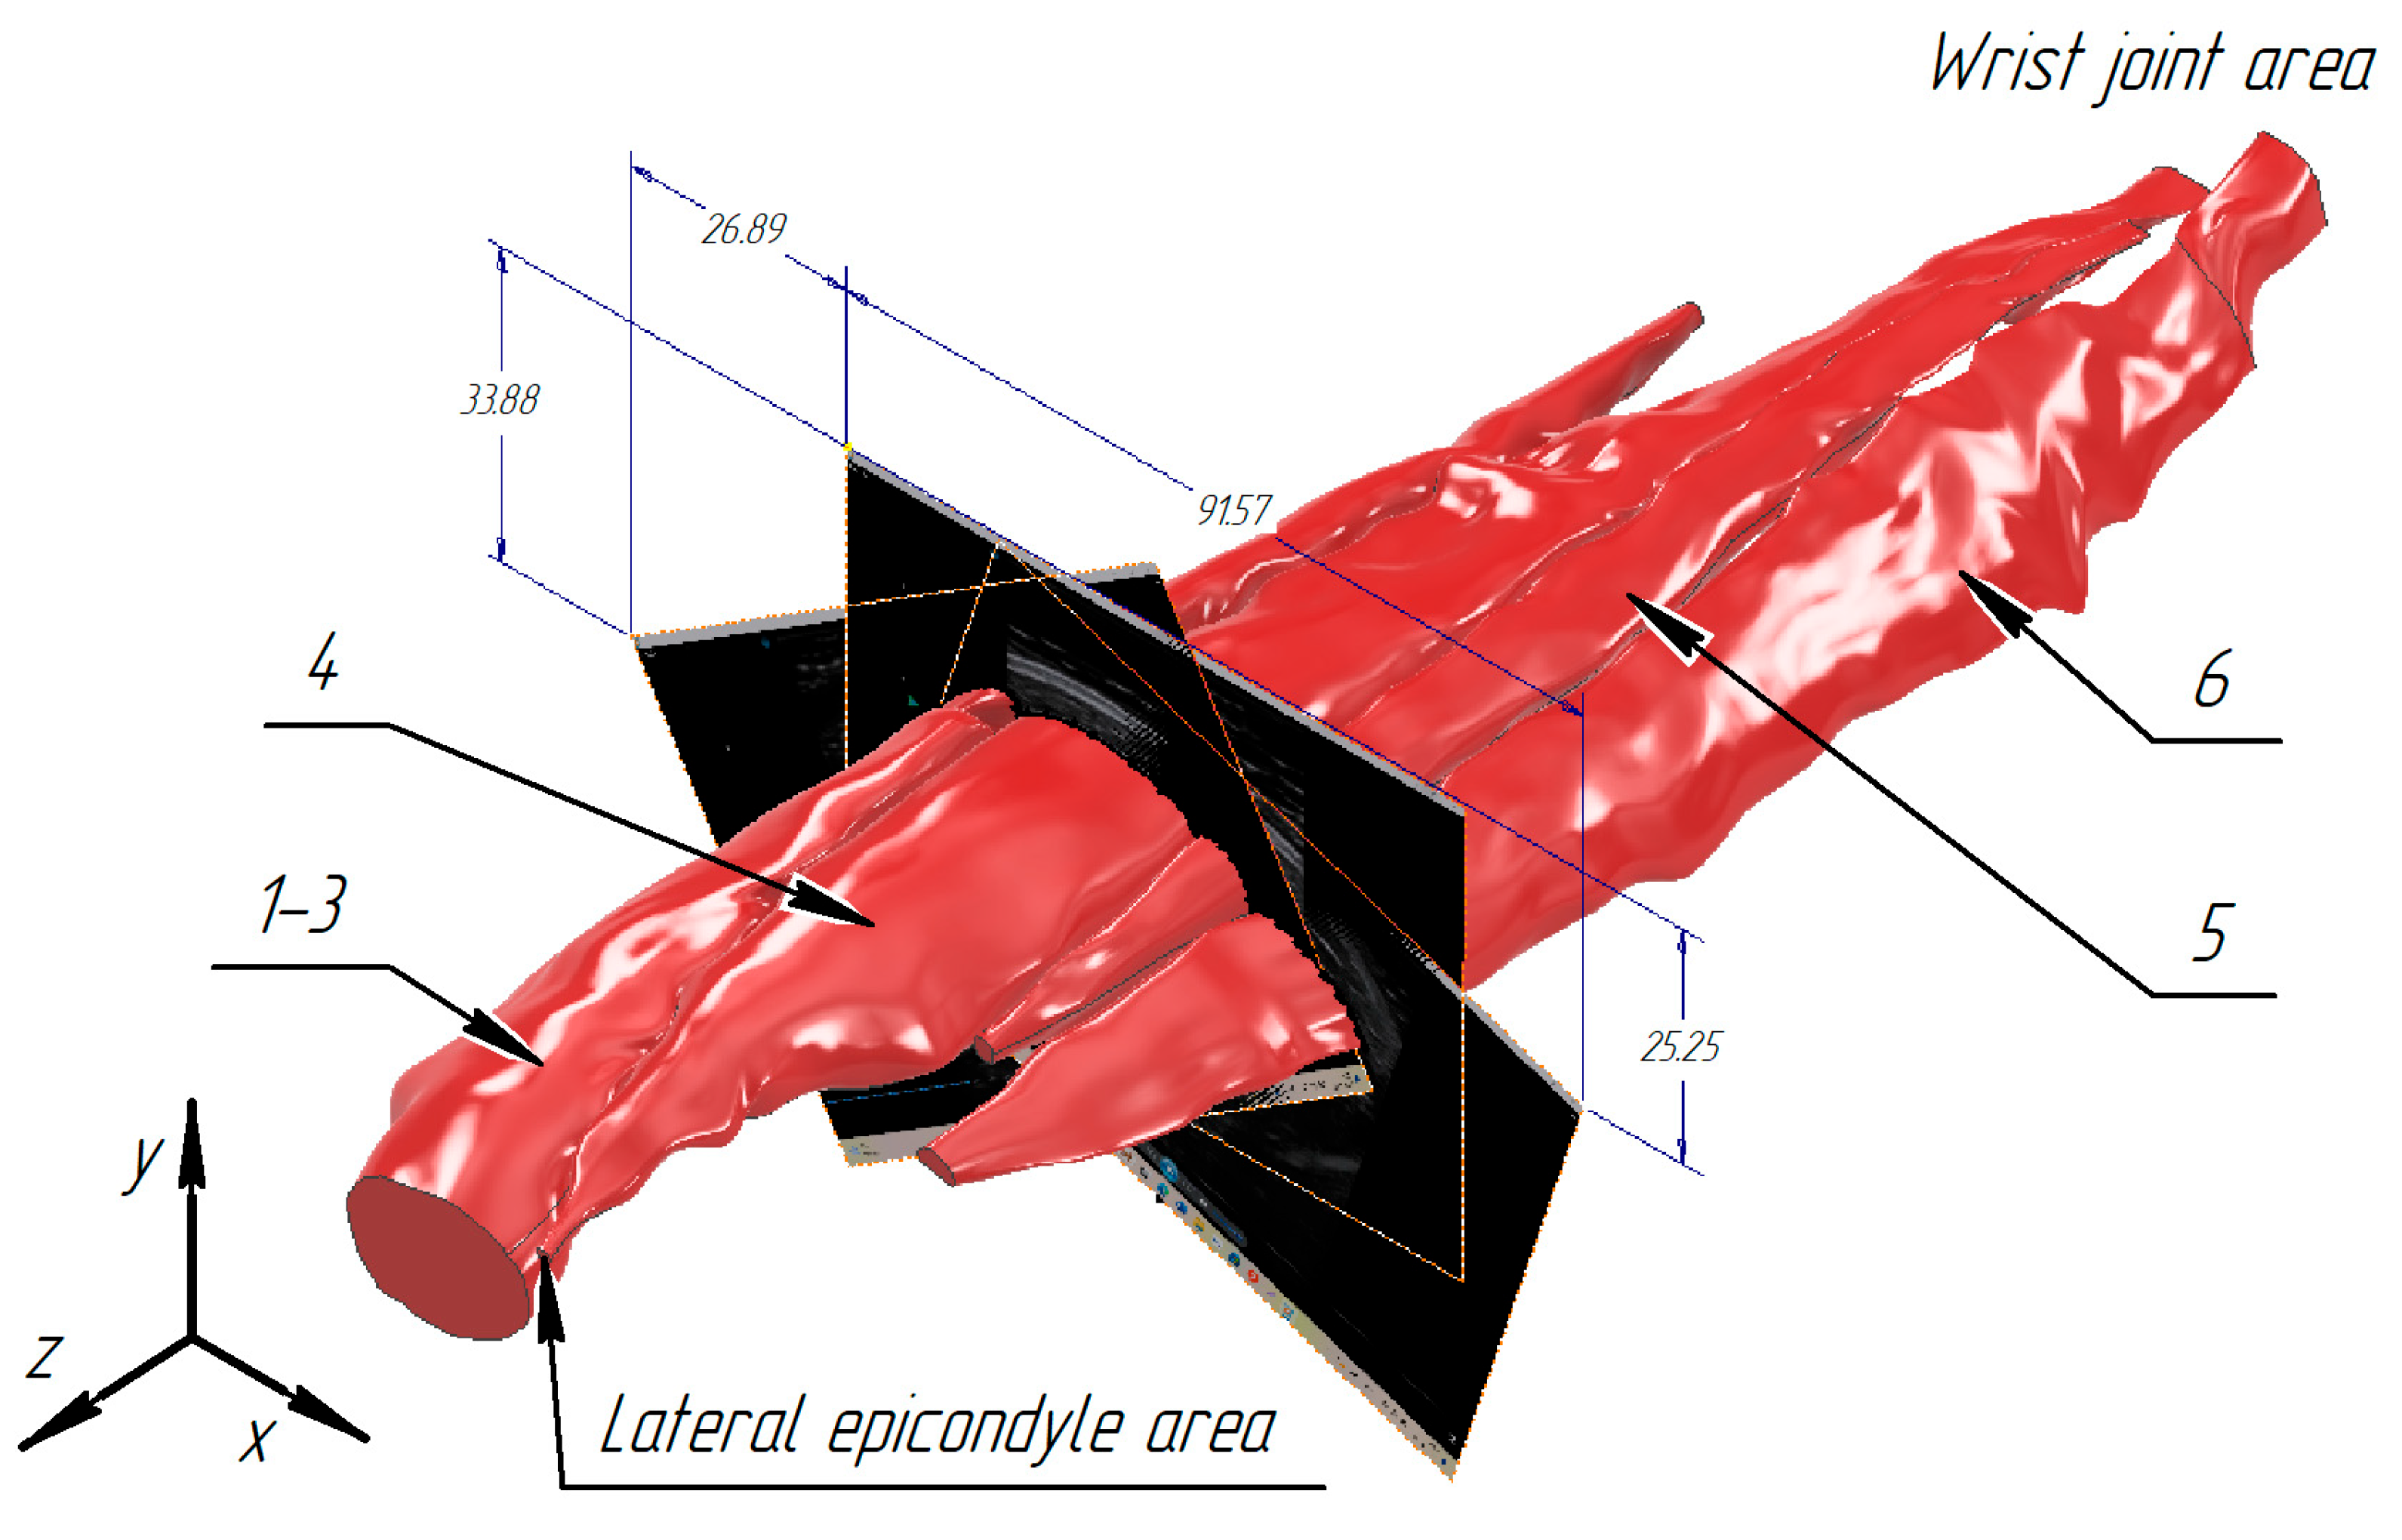

3.1. Construction of the Forearm Muscles’ Volumetric Models

3.2. Verification of the Methodology for Constructing the Soft Tissue Volumetric Models